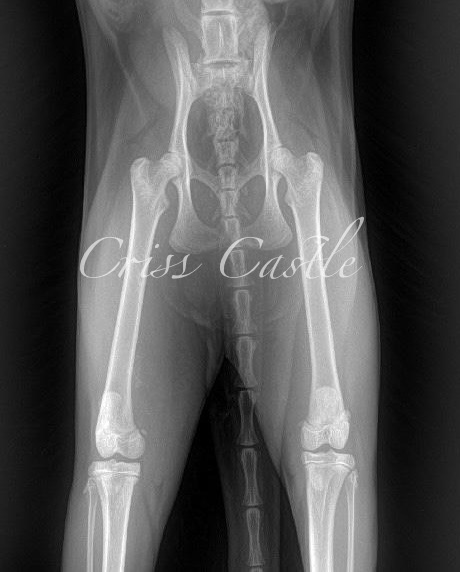

Hip X-Ray Results

Below are the current hip x-ray results for each Criss Castle breeding cat.

Note that as the cats continue to grow, this page may be updated with new results.